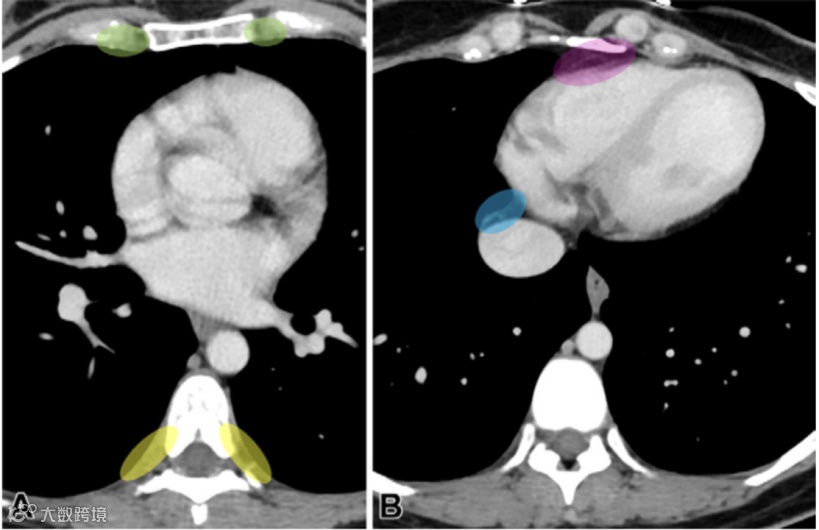

图5.纵膈淋巴结影像学示意图。

A-C为横断位;D为冠状位。气管的左侧壁,而非中线,作为2R和2L(A中的白线所示)以及4R和4L站点之间的边界(B中的绿色和蓝色区域所示)。Arch = aortic arch(主动脉弓),Asc. Ao = ascending aorta(升主动脉),Azygos V. = azygos vein(奇静脉),BCA = brachiocephalic artery(头臂动脉),Bronc. Inter. = bronchus intermedius(中间支气管),Des. Ao = descending aorta(降主动脉),Esp = esophagus(食管),LBCV = left brachiocephalic vein(左头臂静脉),LLL bronc = left lower lobe bronchus(左下叶支气管),LPA = left pulmonary artery(左肺动脉),LSCA = left subclavian artery(左锁骨下动脉),MPA = main pulmonary artery(主肺动脉),RBCV = right brachiocephalic vein(右头臂静脉),RPA = right pulmonary artery(右肺动脉),SVC = superior vena cava(上腔静脉),Tr = trachea(气管)。

图6.位于胸部但并非区域性胸部淋巴结受累的区域。

(A)在左心房水平获取的轴位CT图像显示了内乳(绿色区域)和肋间(黄色区域)区域。

(B)在心脏基底水平获取的轴位CT图像显示了横膈上淋巴结前组(粉色区域)和中组(蓝色区域)区域。腋窝淋巴结或上述图像中展示的淋巴结区域,均被归类为远处转移(M1)。